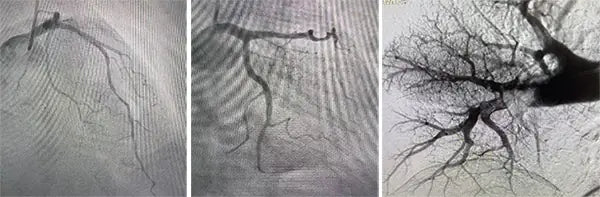

On March 21, under local anesthesia, physicians accessed the femoral vein and deployed the Tendvia™ Pulmonary Thrombectomy System. Through real-time imaging, large thrombi were successfully removed using dual suction and retrieval stent technology, significantly improving pulmonary circulation and oxygenation.

Following thrombectomy, the team conducted coronary angiography to evaluate myocardial injury. The results showed 50–60% stenosis in the left anterior descending artery but no acute blockage, allowing physicians to optimize medication therapy instead of performing unnecessary interventional or thrombolytic procedures.